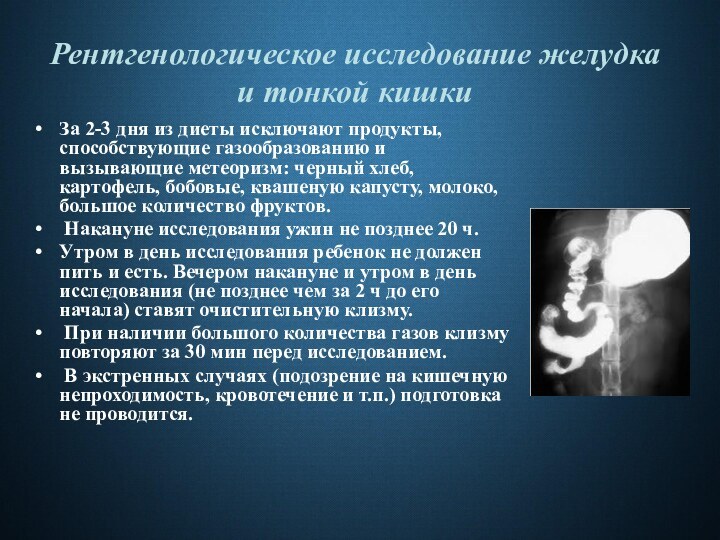

Рентгеноконтрастные Исследования Кишечника: Визуализация и Методики

Раздел: Иллюстрированный журнал